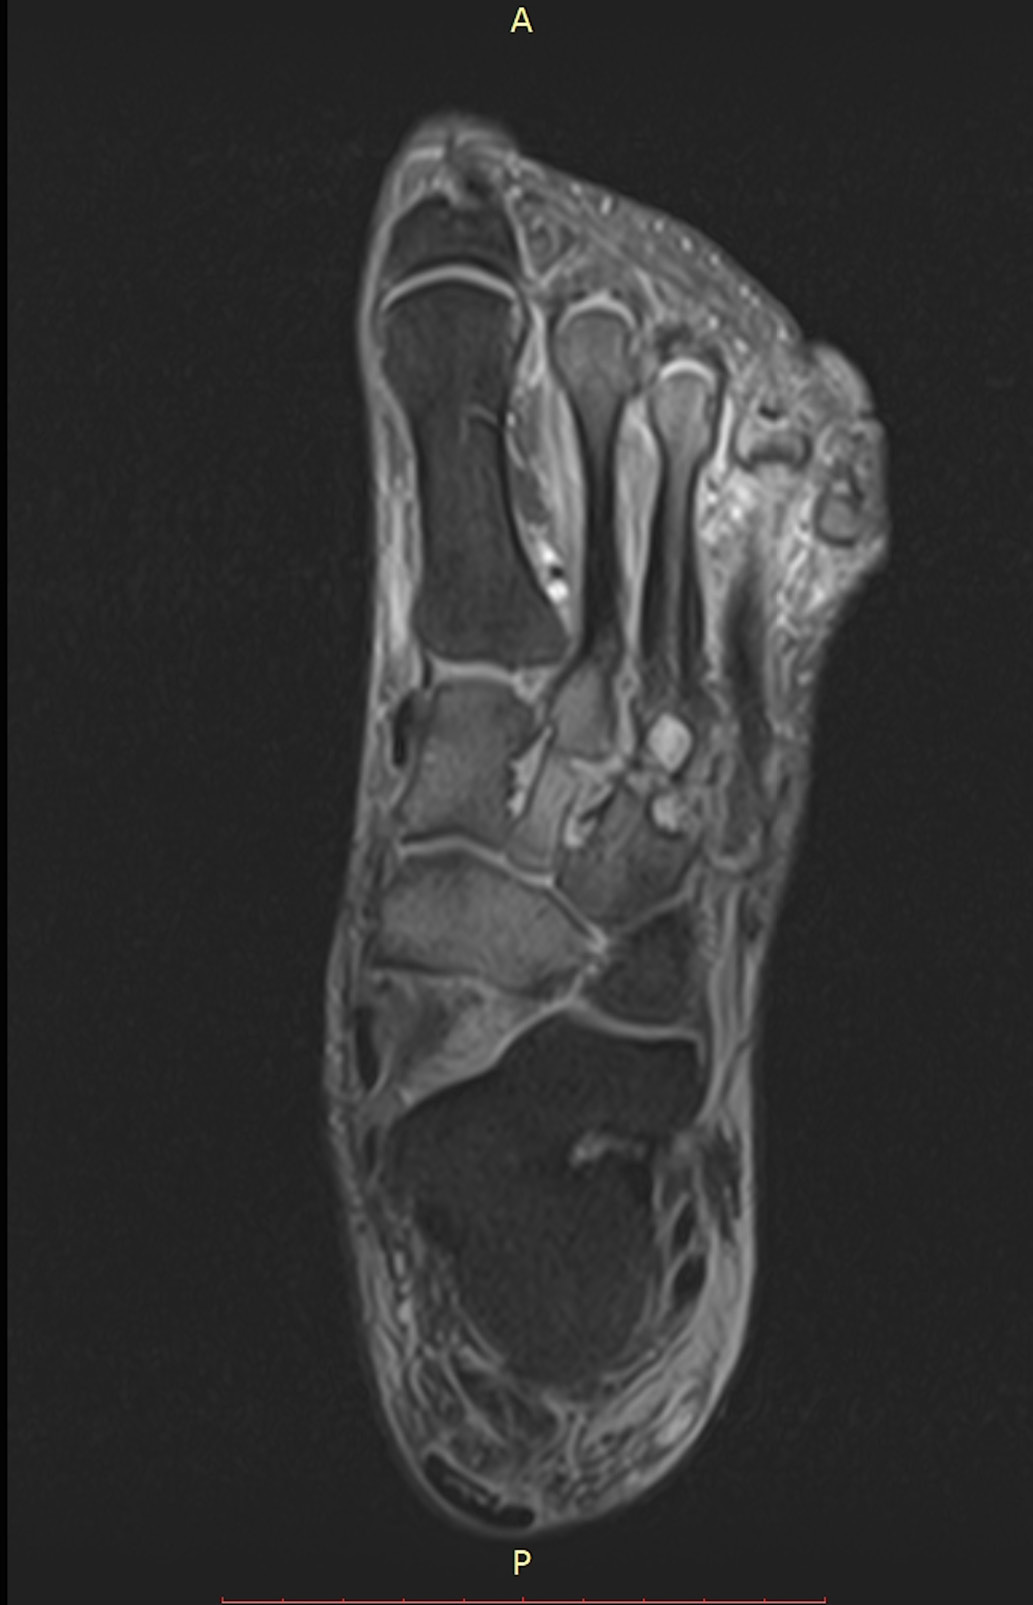

21.01.2019 г. выполнена МР-томография, на которой отмечена положительная динамика: исчезновение отека костного мозга в пяточной, кубовидной и таранной костях. Патологические изменения в других костях сохраняются (рис. 8, 9). ИРП преобразована в съемную, однако не отменена в связи с данными МРТ и сохранением температурного градиента на прежнем уровне. В настоящее время пациент продолжает иммобилизацию. Контрольный осмотр планируется на конец февраля, а рентгенография стопы – на март 2019 г.

Рис. 8. Исходная МР-томограмма стопы. Режим жироподавления. Сагиттальный срез. Отек костей предплюсны, проксимальной головки II плюсневой кости, кубовидной, таранной, пяточной костей. Деструкция клиновидной кости.

Рис. 9. МР-томограмма стопы от 01.2019. Режим жироподавления. Сагиттальный срез. Отек кубовидной кости уменьшился, отек таранной и пяточной костей не определяется. В остальном – без динамики.